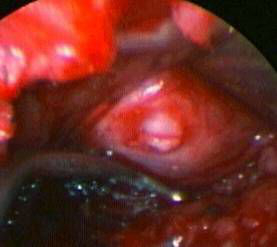

vue peropératoire

Hernie discale

vue peropératoire (microscope)

Le principal but de l’intervention, est de supprimer la compression du nerf, libérer la racine nerveuse comprimée en enlevant la hernie discale. Il faut également vider le disque en enlevant les fragments de nucleus qui sont abîmés et qui pourraient être à l’origine d’une nouvelle hernie discale. Parfois, si des phénomènes arthrosiques s’ajoutent à la hernie, il faut libérer le nerf comprimé par un ostéophyte (bec de perroquet) ou par un ligament trop épais.

L’utilisation du microscope opératoire est possible. La cicatrice est plus petite, la voie d’abord est limitée à l’espace compris entre deux vertèbres sans devoir s’élargir sur l’os ou les articulations. Le geste est plus fin et le chirurgien distingue mieux le nerf et ce qui l’entoure. Souvent, l’intervention est plus rapide, moins hémorragique et les suites plus simples. Le saignement durant l’intervention est minime.